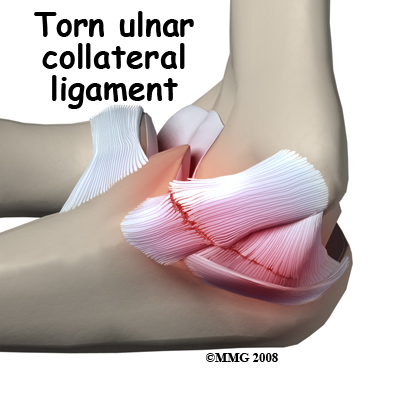

The ulnar collateral ligament (UCL) can become stretched, frayed or torn through the stress of repetitive throwing motions.

The ulnar collateral ligament can become stretched, frayed or torn through the stress of repetitive throwing motions. If the force on the soft tissues is greater than the tensile strength of the structure, then tiny tears of the ligament can develop. Months (and even years) of throwing hard causes a process of microtears, degeneration, and finally, rupture of the ligament. The dominant arm is affected most often. Eventually the weakened tendon my rupture completely causing a pop and immediate pain. The athlete may report the injury occurred during a single throw, but the reality is usually that the ligament simply finally became weakened to the point that it finally ruptured.

If the ulnar collateral ligament has been injured acutely due to a fall on the outstretched arm, a direct repair of the ligament may be possible. If the ligament has pulled off the bone, it may be reattached with sutures through holes drilled in the bone. If the ligament is damaged by constant overuse and is not strong enough to restore stability to the elbow joint if it is simply re-attached or repaired, then the ligament must be replaced with a new ligament. This is termed a ligament reconstruction. During a reconstruction, the ulnar collateral ligament along the medial (inside) of the elbow is replaced with a tendon graft harvested from somewhere else in the body (autograft). One common technique used to replace the damaged ulnar collateral ligament is called the technique.